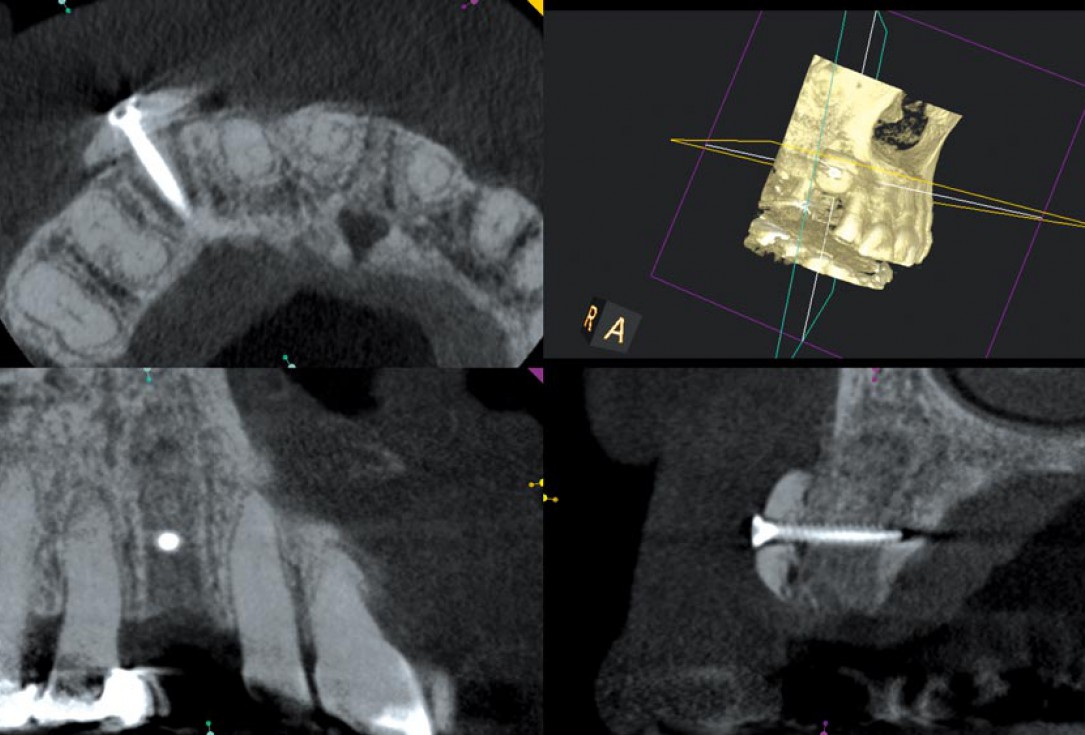

03/12 - Initial CBCT scan

Block augmentation with maxgraft® in the maxilla - PD Dr. Dr. F. Kloss